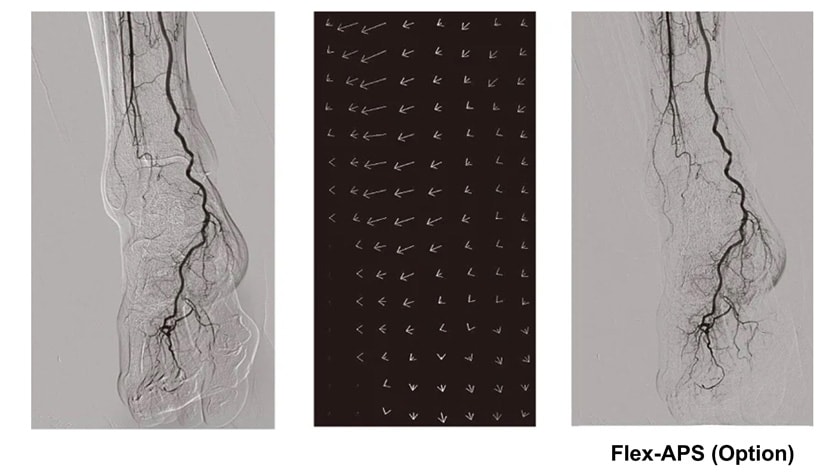

- Crossover Angiography System - Trinias series with SCORE Opera

Crossover Angiography SystemTrinias series

with SCORE Opera

The Trinias series with SCORE Opera is a Crossover Angiography System developed to provide solutions for the evolving challenges in medical treatment centers. This system is designed based on three core principles: ALARA (As Low As Reasonably Achievable) Design, Lean Design, and Sustainable Design.

IVR procedures are becoming increasingly complex and sophisticated, and require angiography systems that can achieve lower radiation doses, less contrast media use, and shorter examination times. Shimadzu's latest Trinias™ series angiography system comes with various features that support minimally invasive procedures ...